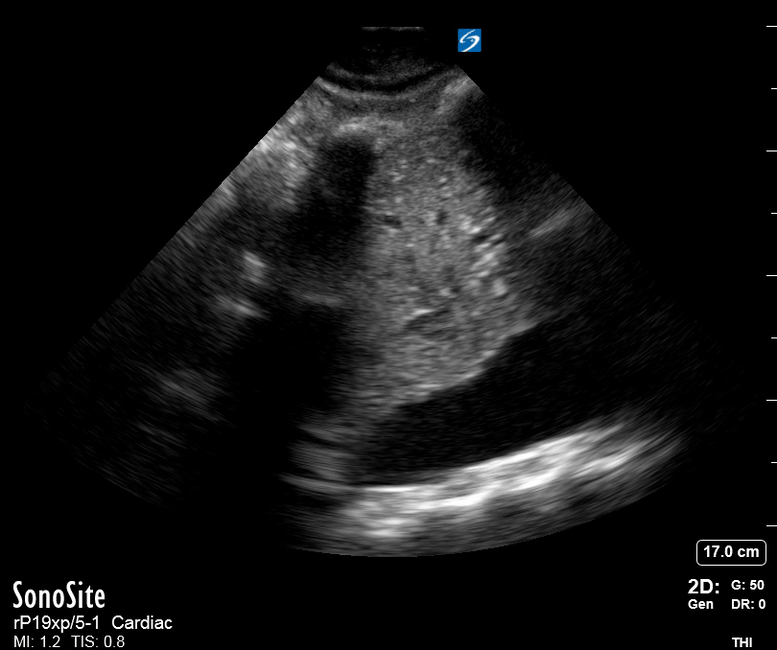

The IVC diameter changes depending on intravascular volume status, and normally, the IVC collapses during spontaneous inspiration. Therefore, the IVC diameter represents a non-invasive method for estimating central venous pressure (CVP). The evidence suggests that in spontaneously breathing patients, there is a good correlation between the sonographic estimation of CVP and values measured with invasive methods (2). IVC filling and CVP, however, allow only a rough correlation with volume status, and the sonographic estimation of preload should at least include the assessment of the LV and the Lung. Thus, it is better to think of IVC filling as an indicator of fluid tolerance, instead of a determinant of fluid responsiveness (6).

IVC exploration is best from the subxiphoid approach with longitudinal and transverse images. The IVC should be assessed in terms of overall size and collapsibility. The diameter is typically measured at its largest (end of expiration) at 1-2 cm distal to where the hepatic veins join the vena cava. An IVC diameter of ≥ 2 cm, especially with minimal or no collapsibility, is considered plethoric and correlates with increased RA pressure. An IVC of < 1 cm, particularly with complete collapse, is considered flat and indicates low preload and potential fluid responsiveness. An IVC diameter between 1 and 2 cm is typically normal.

PITFALLS

In a long-axis view, beware of not sliding off the centre of the vessel, as this will underestimate the size of the IVC and overestimate its collapse. Obtaining long and short axis views may help avoid this pitfall. Another mistake is confusing the descending aorta for the IVC, particularly when scanning in long-axis. Although the IVC may appear to pulsate, the aorta has a thicker wall, and its position is to the patient’s left. Following the IVC upwards will reveal the hepatic veins junction and the entrance to the RA, while the aorta will travel behind the heart. The IVC moves both anterolaterally and craniocaudally with inspiration, and this should be considered during visualization or measuring. For this very reason, measuring in M-mode is not recommended as it would not be accurate.